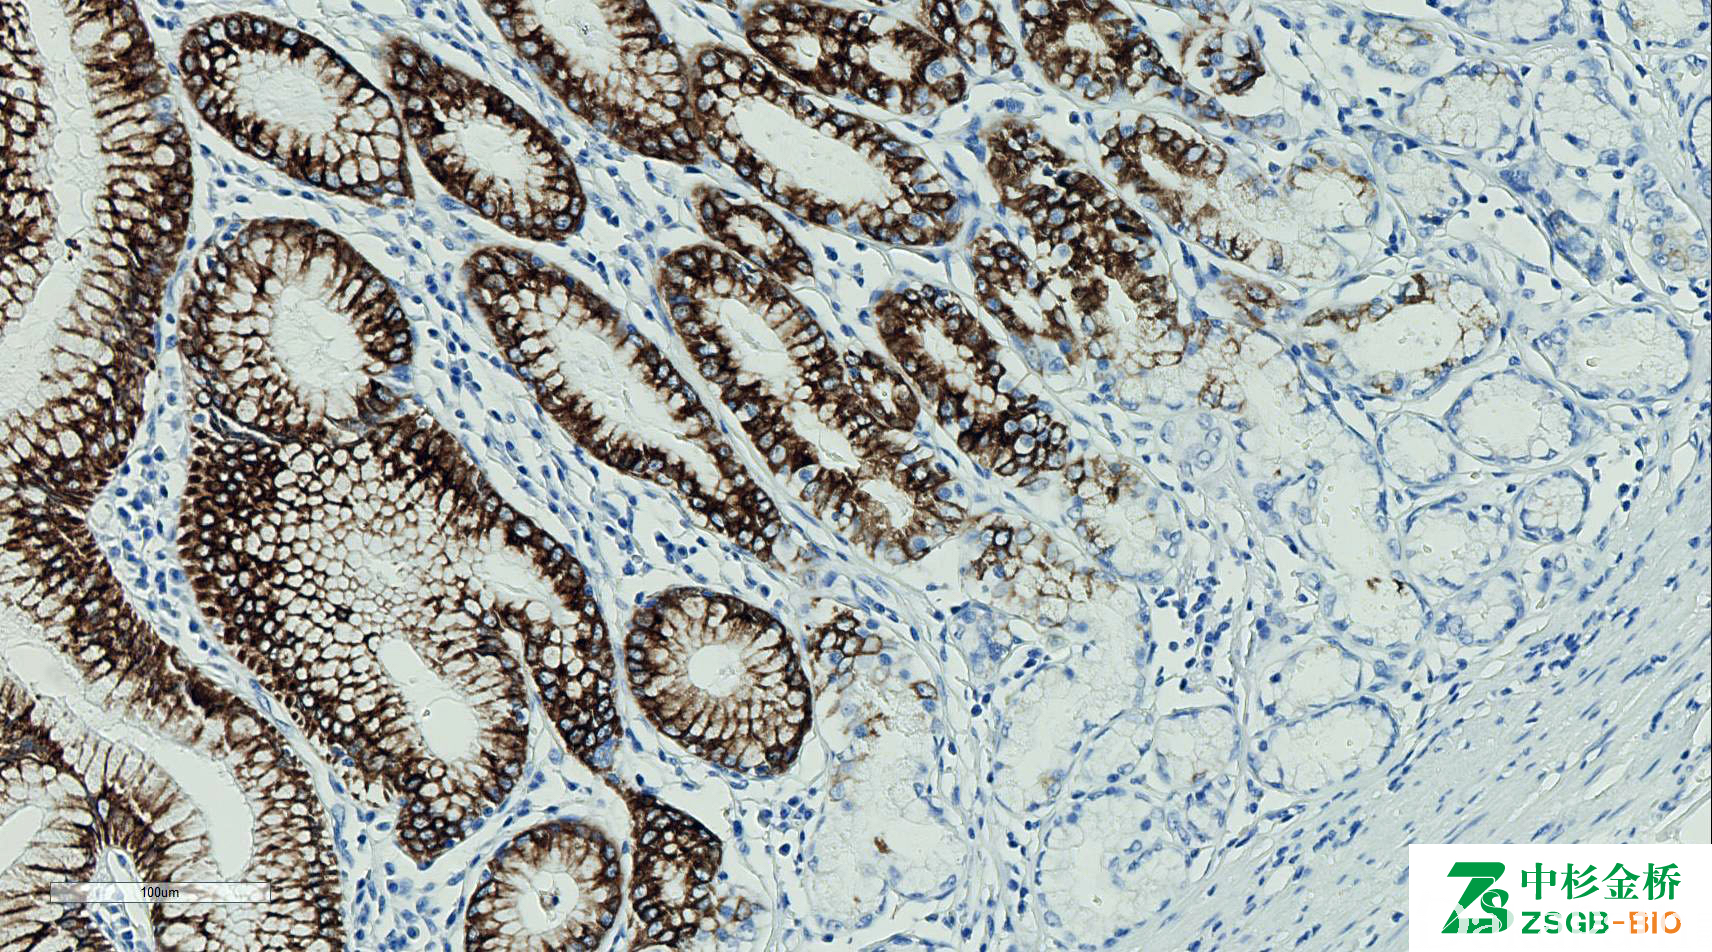

MUC5AC

正常只表达于胃型上皮(包括壶腹),又称胃型黏液。MUC 系列用于黏液性肿瘤黏液上皮分化类型的鉴别。

信号定位: 胞质